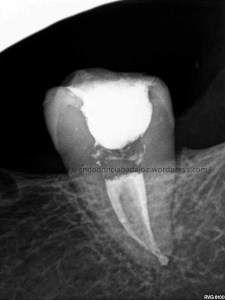

En esta entrada subimos un video de como tratamos un caso que nos mandan , se trata de una pieza 4.6. Tras una exploración radiográfica y la explicación del paciente, que nos refería varios intentos por parte de su odontólogo, sospechamos de una perforación en furca. Con la presencia del M.T.A, este tipo de casos no serán complicadas de tratar y presentan un porcentaje elevado de éxito. Sabemos que depende de la localización, el tamaño y el tiempo que ha transcurrido.